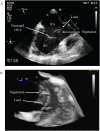

Implantable cardioverter-defibrillator endocarditis is a rare and potentially life threatening complication of brucellosis of difficult management for clinicians. We report an unusual case of pacemaker-related endocarditis due to Brucella melitensis in a patient with previous history of neurobrucellosis. Our patient was admitted to a hospital with severe swelling of his pacemaker pocket implanted 8 years earlier for sick sinus syndrome. Although pocket site cultures were positive for Brucella but blood cultures were not and serologic titer by the Rose Bengal test was positive. Transesophageal echocardiography showed two vegetations on the pacemaker leads. The patient was treated with doxycycline, rifampin and gentamicin with full recovery and the entire pacemaker apparatus was surgically explanted. Interestingly, two year prior this admission, the patient presented with meningoencephalitis diagnosed with neurobrucellosis proven by positive growth of Brucella mellitensis from the CSF. The patient was treated with doxycycline, rifampin and gentamicin with full recovery and the pacemaker had been removed. Reports of Brucella infection of prosthetic implants and devices have increased over the past decade. Consequently, potential relapsing of the disease and occupational exposure to Brucella should be considered in the differential diagnosis and management of cardiac device infection.